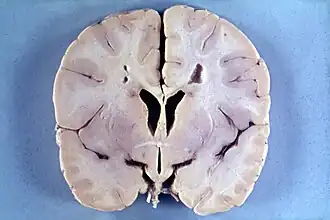

Болезнь Александера — патологоанатомически демиелинизирующая лейкодистрофия — заболевание, проявляющееся в раннем детском возрасте (до года), является наследственным. Аутосомно-доминантный тип передачи. Свойственны нарушения метаболизма в астроцитах. Наблюдается задержка умственного развития, увеличение массы головного мозга, высокая температура, судорожные припадки, слабый мышечный тонус, прогрессирующая гидроцефалия, пирамидные знаки. У детей Болезнь Александера протекает катастрофически, иногда наступает смертельный исход при проявлениях спастической тетраплегии и децеребрационной ригидности. У взрослых более медленное течение заболевания, с ремиссиями и остановками. Прогрессирует заболевание быстро, рано наступает летальный исход.

При магнитно-резонансной томографии головного мозга (МРТ) при болезни Александера выявляется демиелинизация различных отделов мозга (при инфантильной и юношеской формах — преимущественно в лобных с распространением на другие области, при взрослой — более выражена в мозжечке и стволе мозга).

Подтверждением заболевания служит обнаружение волокон Розенталя (что возможно при биопсии мозга или уже после смерти при вскрытии).